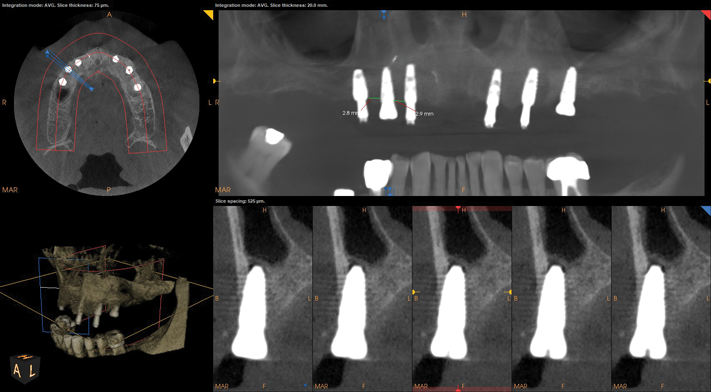

CBCT evaluation indicated that all four implants were healthy, and a decision was made to place two more implants. The plan called for one implant to be placed on each side to create an all-on-six solution. In the maxillary right quadrant, an implant would be placed between the two existing implants. The complexity of maintaining 3 mm of adequate space between each implant in the right quadrant for hygiene maintenance and adequate blood supply necessitated the use of guided surgery, as failure to maintain the 3 mm inter-implant spacing can result in severe bone loss and peri-implantitis.19In the left quadrant an implant was planned posterior to the most distal implant, thus requiring the implementation of the OD sinus lift protocol described in Case 1 (Figure 10).

Fig 10. CBCT revealed relatively non-complex implant placement on

the maxillary right side for the maintenance of 3 mm between each

implant and less than 6 mm residual bone height on the maxillary left

side.